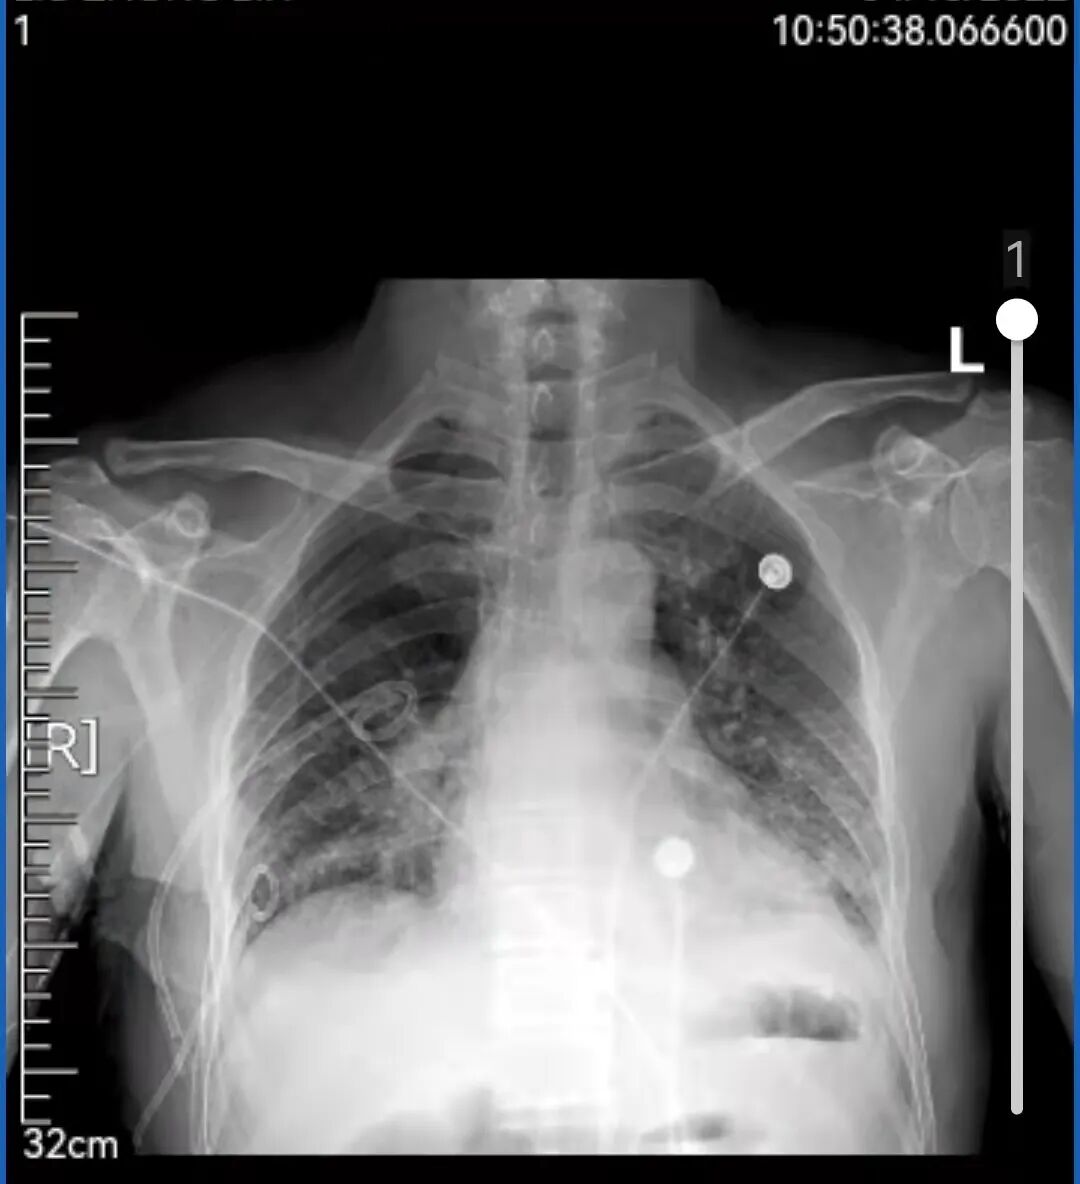

60岁的刘先生平时身体一直不错,登山、跳绳、骑行样样行。像他这样的年龄血压、血糖等都在正常值范围内,身体素质甚至比年轻的小伙子还好。因为没有这疼那痒,五年内从没体检过。 上个月不小心被车撞了一下,到辽宁省肿瘤医院拍了个肺部CT进行检查,这一查不要紧,除了受损的两根肋骨外,“眼尖”的医生居然在CT片子上发现了一个“恶魔”,在其右肺上叶有一个接近5cm的肺结节。 影像资料 辽宁省肿瘤医院胸外科团队接诊后,耐心地询问刘先生,可刘先生既没有吸烟史也没有癌症家庭史,每天在公园暴走上万步的刘先生,会跟“肺癌”这两个字联系在一起吗? 影像资料 为了不给刘先生及其家属带来恐慌,又不能耽误病情,胸外科团队请来了专家为其进行多学科会诊(MDT),“我们不敢冒然行事,也不敢错过手术最佳时机,因为从这个肺结节的形态上来看,如果是肺癌的话,行手术根治术+淋巴清扫,预后效果应该还是不错的”。 手术中 经多学科会诊,专家们建议为刘先生行CT引导下穿刺,以进一步明确病理。病理结果出来后,跟专家们的预想差不多,病理提示“肺腺癌”,胸外科为刘先生做了单孔胸腔镜下的肺癌根治术+淋巴清扫术。术后刘先生恢复很快,5天就出院了。因为是早期肺癌,发现得早,及时手术切,刘先生并不需要化疗、放疗,刘先生悬着的心终于放下了,说道“要不是这场车祸,不然还不知道什么时候会发现,也有可能发现时就是晚期了呢” 早期肺癌治愈率高,定期体检是关键。祸兮福之所倚,福兮祸之所伏。短短一个月内,刘先生经历了“车祸——肺结节——肺癌——手术根治”的跌宕人生。像刘先生这样因为外伤检查住院而意外发现早期肺癌的患者,医院也收治了不少。因为早期肺癌相当隐匿,几乎没有什么症状。如果缺乏定期体检,不做胸部CT,早期肺癌是难以发现的。而等患者发现时就已经到了中晚期了,不仅治疗复杂费钱,效果还不好。 辽宁省肿瘤医院胸外科专家介绍,早期肺癌治愈率较高,其中原位癌及微浸润腺癌治愈率可达90%--100%,且不需要放疗、化疗,治疗费用低,生存质量也高。而中晚期肺癌的五年生存率只有20%--50%。所以,定期体检非常重要。但值得注意的是,大部分肺结节是良性的,只有30%--40%的肺结节可能是早期肺癌。即便是早期肺癌,通过微创手术切除治疗效果也较好。 关注!关注!关注! 辽宁省肿瘤医院疫情期间 门诊就诊攻略 辽宁省肿瘤医院互联网医院 “在线复诊”上线了 稿件、图片来源:胸外科一病区 编辑:刘换 洪流 责编:郑阳 你“在看”我吗?